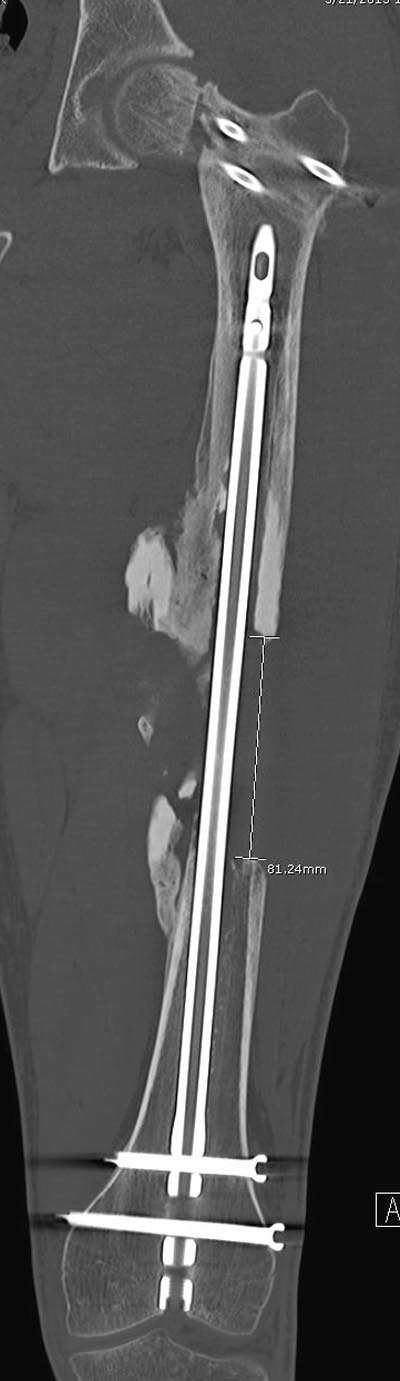

Здесь выставлен ренгенограммы больного, ему 21, травму получил в результате высокоскоростной погони на украденной машине, которая закончилась смертью трех остальных “боевых комрадов”. Начатую коллегой открытую операцию на шейке пришлось закончить мне, установкой винтов и ретроградной фиксацией бедра. Выписка в обычное сроки и наблюдался амбулаторно. Каждый раз напоминали о возможности осложнений ввиде несращения! По истечению 4 месяцев появились признаки варусной деформации. На СТ срезах несращение шейки и бедра. Риминг, замена на более толстый гвоздь и вальгусная остеотомия.

Сразу скажу, что пациент вчера (8.04) прооперирован - артротомия, остеосинтез мыщелков большеберцовой кости канюлированными винтами, открытая репозиция отломков бедренной кости, ретроградный БИОС, остеосинтез надколенника (центральных его отломков) спицами с проволочной петлей. Двухкратная попытка закрытой репозиции шейки на операционном столе после синтеза бедра - абсолютно неэффективна. Учитывая продолжительность и травматичность операции, шейка отложена на 2-й этап. Плечо наверное на 3-й (если вообще делать). Снимки постараюсь предоставить, но чуть позже.